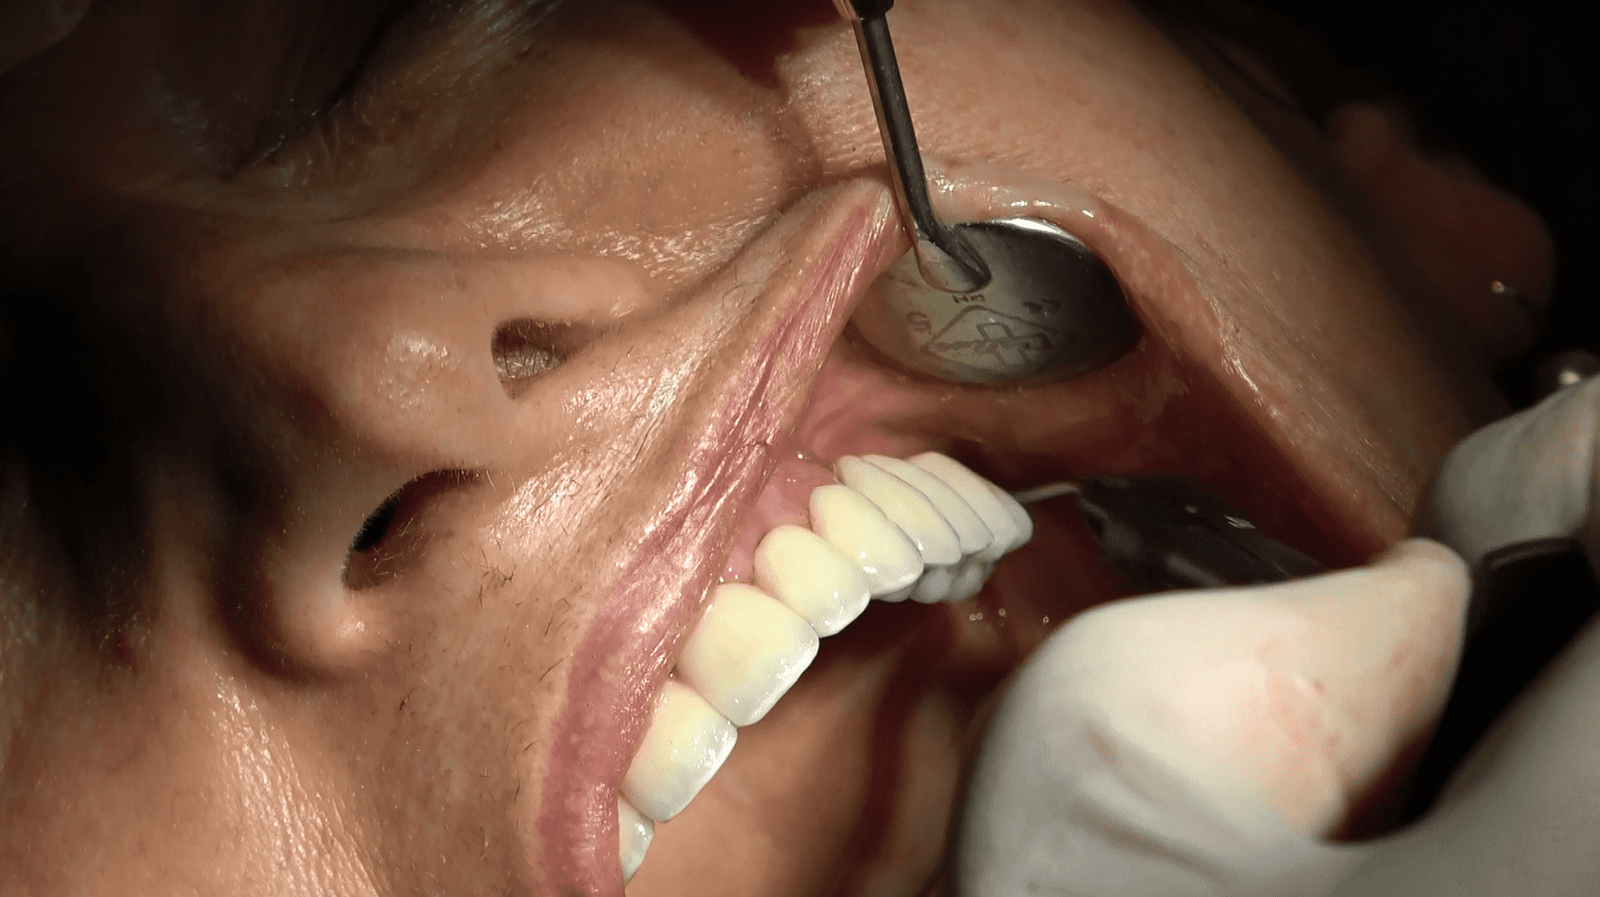

- Carico Immediato: Grazie all’implantologia sottoperiostea, il paziente ha beneficiato del carico immediato, ottenendo denti fissi funzionali in un tempo incredibilmente breve.

Il paziente, dopo un periodo di recupero relativamente breve, ha ripristinato la funzionalità e l’estetica del sorriso. Questo caso dimostra come l’implantologia sottoperiostea possa essere una soluzione efficace anche per pazienti con atrofia ossea estrema, offrendo risultati duraturi e soddisfacenti.